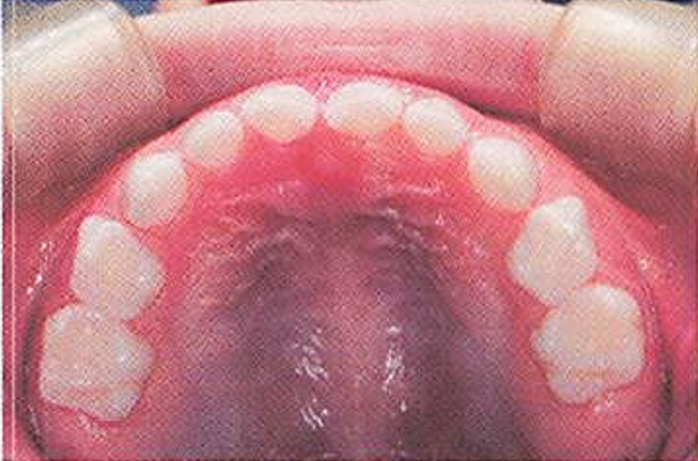

午後-91

8歳の女児。定期歯科健康診査で来院した。口腔内写真(別冊午後 No.36)を別に示す。 口腔内でみられるのはどれか。2つ選べ。

a.上唇小帯の異常

b.乳臼歯部の咬耗

c.前歯部の交叉咬合

d.Hellmanの歯齢ⅢB期

解答を見る

b.c